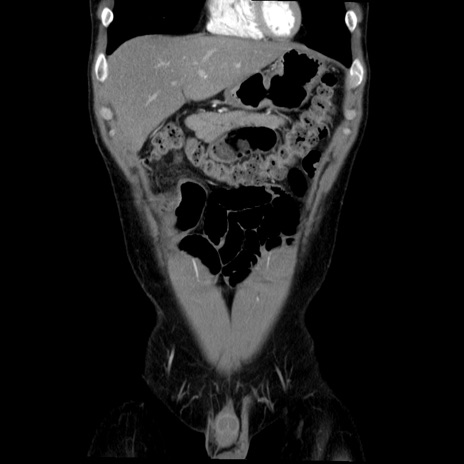

症例36(冠状断像)

【症例】20歳代 男性

【主訴】心窩部痛

【現病歴】今朝より上腹部痛あり。一旦軽快していたが再度出現したため救急要請。昨日夕に白身の魚を含む刺身を食べた。

【身体所見】BP 136/89mmHg、HR 74/min、BT 37.0℃、腹部:膨満、軟、心窩部に圧痛あり。反跳痛なし、筋性防御なし、腸雑音やや亢進あり。

【データ】WBC 17700、CRP 0.48